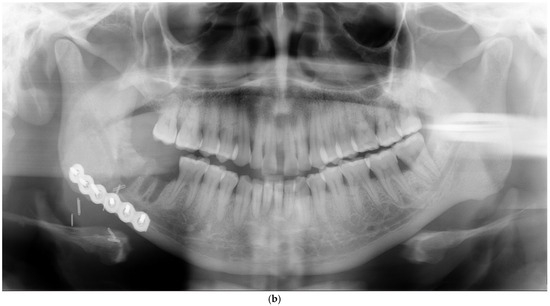

| Anterior part (symphysis/parasymphysis) | 5 | 2 | 3 inadequate reductions, 2 nonunions with infection | ||

| Angle | 3 | 2 | 1 inadequate reduction, 1 infection, 1 nonunion with infection | ||

| Body | 3 | 0 | 3 inadequate reductions | ||

| Condyle | 3 | 1 | 2 inadequate reductions, 1 broken plate | ||